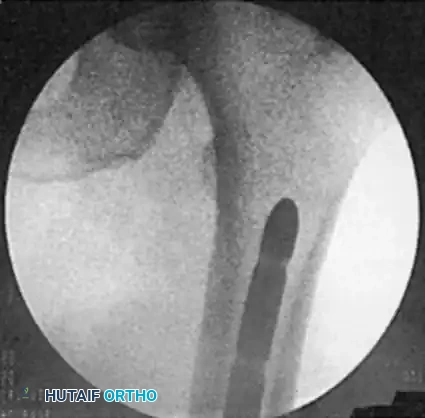

Distal Locking (Perfect Circle Technique):

* Align the C-arm perfectly perpendicular to the nail so the distal locking hole appears as a "perfect circle" rather than an ellipse.

* Make a stab incision directly over the hole.

* Using a radiolucent drill drive, advance the drill bit directly down the path of the fluoroscopic beam through the near cortex, through the nail hole, and out the far cortex.

* Measure the depth and insert the appropriate locking screw.